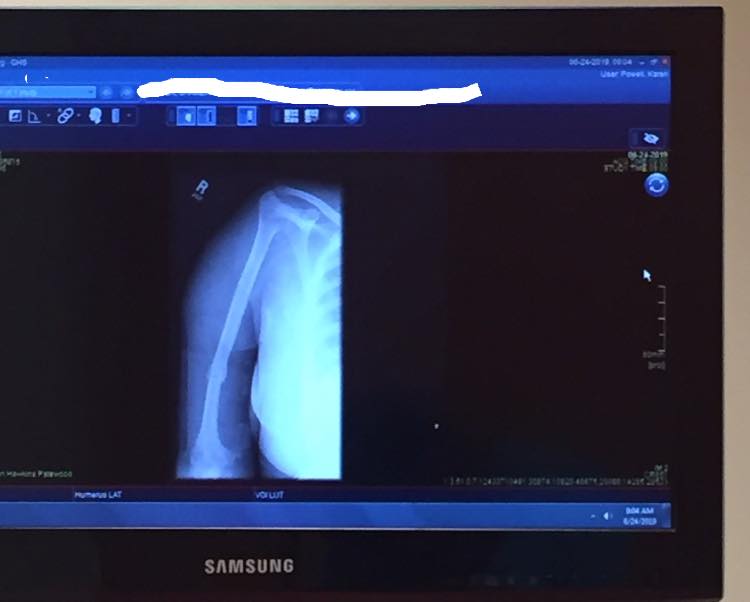

I was trying to end my last year at Lander with a bang and it backfired. The goal was to figure out a way for Lander to be more accessible to their students with disabilities. I had been meeting with one of the vice presidents on campus to make it happen. On May 1st at 1 pm is the time we picked for the “accessibility tour.” I had different parts on campus that I wanted to take him around and throw out ideas on the way it could be more accessible. We left the library and headed towards the pool. I was explaining to him that they should put a pathway that led to the entrance. He suggested that I go up this grassy, hilly area. I’m assuming so he could get a better understanding of my suggestion. As I started up that hill, my scooter (use it to get around campus) and I went sideways. All my body weight went to my arm. It’s been so long since I’ve felt that kind of pain. It felt like I could feel the dislocation of my arm. The VP called campus safety. I did not want to be touched. They had to call the ambulance to get me. When I got to the ER it took them forever to give me something for pain. Without a doubt one of the worst days of my life. Oh and did I mention, this was the week before graduation? So yeah, I walked across the stage with a cast on my arm and not to mention, I still needed to get through the exams and I didn’t, still haven’t taken my graduation pics.

Thing is, the last thing a person EVER wants to do is a break, especially the older you get and sucks even worse when you’re a disabled individual. The types of disabilities vary, and the seriousness of the breakage ranges. For me, my bones and joints are already stiff and fragile. So, it’s a possibility that it has become even fragile and stiff and the healing process may or may not be the same as it would be for someone who’s not disabled. Luckily, I know that God creates miracles. My arm healed in the normal predicted time. Unfortunately, as a result of the break, my arm has become a little more stiff. It sucks because I already had limited mobility in my right arm, but I make the best of it and keep pushing.